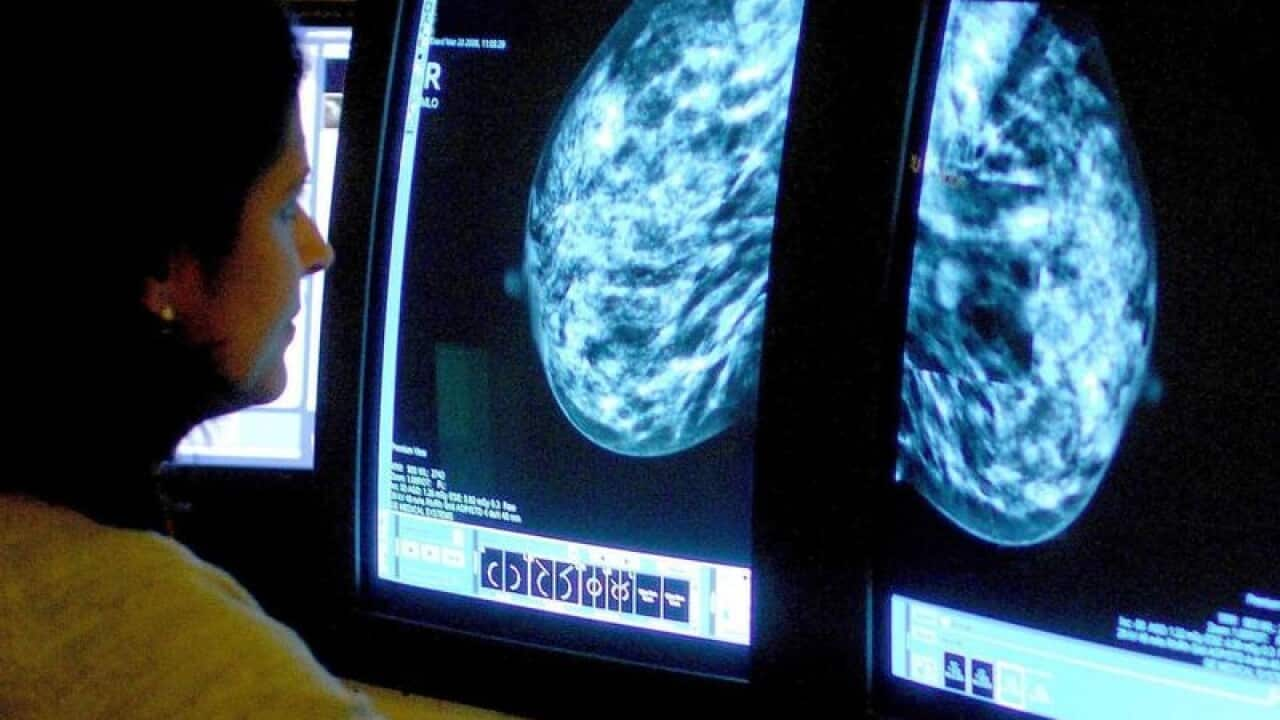

전세계에서 유방암 발병률이 가장 높은 국가 중 하나인 호주, 하지만 사망률은 낮은 것으로 나타났습니다. 어떤 이유 때문일까요?

최신 연구에 따르면 호주는 유방암 발병률이 세계에서 높은 국가 중 하나지만 유방암 사망률은 해마다 감소하고 있는 것으로 나타났습니다.

호주와 뉴질랜드의 경우 유방암 발병률이 매우 높게 나왔지만, 유방암 사망률은 상대적으로 낮게 나왔습니다.

에스터만 교수는 “예상치 못한 일이 아니라고 말하는 이유는 호주는 세계 최고의 검진 프로그램 중 하나를 가지고 있으며 이런 검진 프로그램을 통해 유방암을 진단하고 있기 때문”이라며 “끔찍한 유방암을 진단할 뿐만 아니라 아직 악성 질환으로 발전하지 않은 작은 종양도 많이 진단한다. 그러므로 세계에서 발병률이 가장 높을 수 있지만 이런 검진 과정 덕분에 생존율 역시 세계에서 가장 높다”라고 말했습니다.

연구에 따르면 호주와 뉴질랜드는 유방암 사망률을 해마다 2.1%씩 낮추고 있는 것으로 나타났습니다.